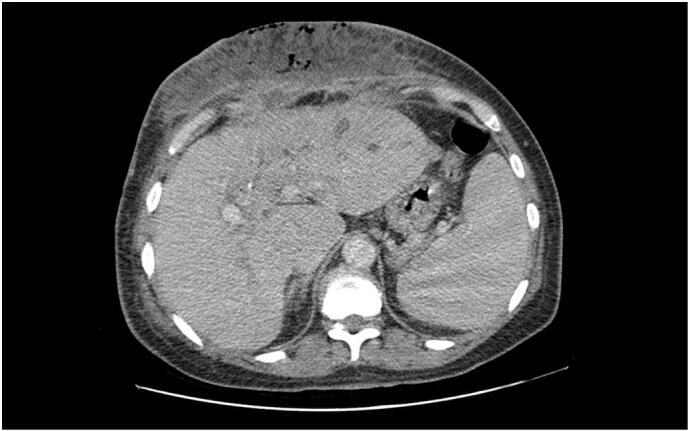

Contrast-enhanced abdominal CT revealed two subcapsular collections in segment III of the liver, measuring 28 × 12 mm and 27 × 14 mm, each with fistulous tracts to the anterior abdominal wall. These extended over 29 mm and 34 mm, respectively, and were associated with extensive subcutaneous soft tissue infiltration, poorly defined necrotic areas spanning more than 10 cm in height, and the presence of subcutaneous emphysematous bullae suggestive of necrotizing fasciitis [Fig. 3, Fig. 4]. Additionally, intra- and extrahepatic biliary dilatation was noted upstream of multiple stones in the common bile duct.

Fig. 3.

Contrast-enhanced abdominal CT scan (axial view) revealing subcapsular hepatic collections in segment III with fistulous tracts extending to the anterior abdominal wall.

The clinical presentation of necrotizing fasciitis can be nonspecific in its early stages, often mimicking cellulitis or abscess. However, the presence of rapidly spreading erythema, crepitus, disproportionate pain, systemic toxicity, and soft tissue gas on imaging should raise strong suspicion [8,9]. In our case, contrast-enhanced CT provided key diagnostic information, revealing hepatic subcapsular abscesses with fistulous communication, soft tissue necrosis, and emphysematous changes consistent with necrotizing fasciitis.